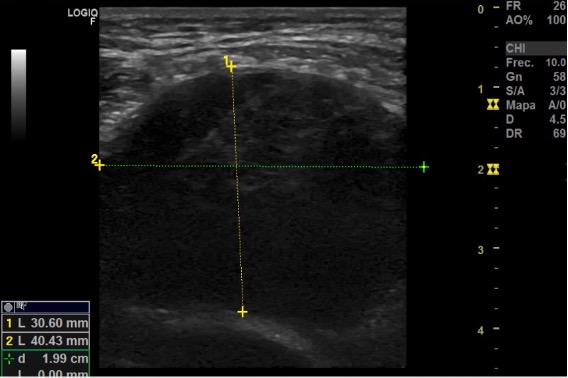

Ecografía: Conglomerado adenopático en axila izquierda. Adenopatía más grande (30 x 40 mm) hipoecogénica, redonda con pérdida del hilio graso, de aspecto infiltrativo y con captación Doppler. Adenopatías infraclaviculares de 27,5 x 12,2 y una glomerulación de 13,9 x 17,1 mm hipoecogénicas con pérdida de estructura normal. Adenopatías perihiliares hepáticas de 9 x 23 mm y otro 26 x 17; perihiliar esplénica de 12 x 4 x 5 mm, e inguinal izquierda de 9,3 x 7,8 mm.